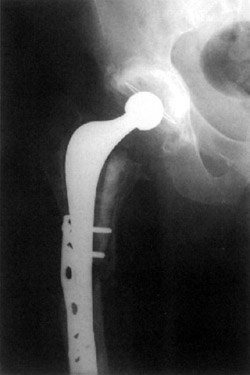

Figure 3. Post op Allogran-N impacted into the acetabulum.

X-rays showed substantial vertical migration of the cup measured at 6mm, this having occurred during the first three months and then stabilizing. Stem subsidence of 2mm was also early but did not progress.

2 years post op

Patient doing well, no further migration of the components and her hip pain has resolved.